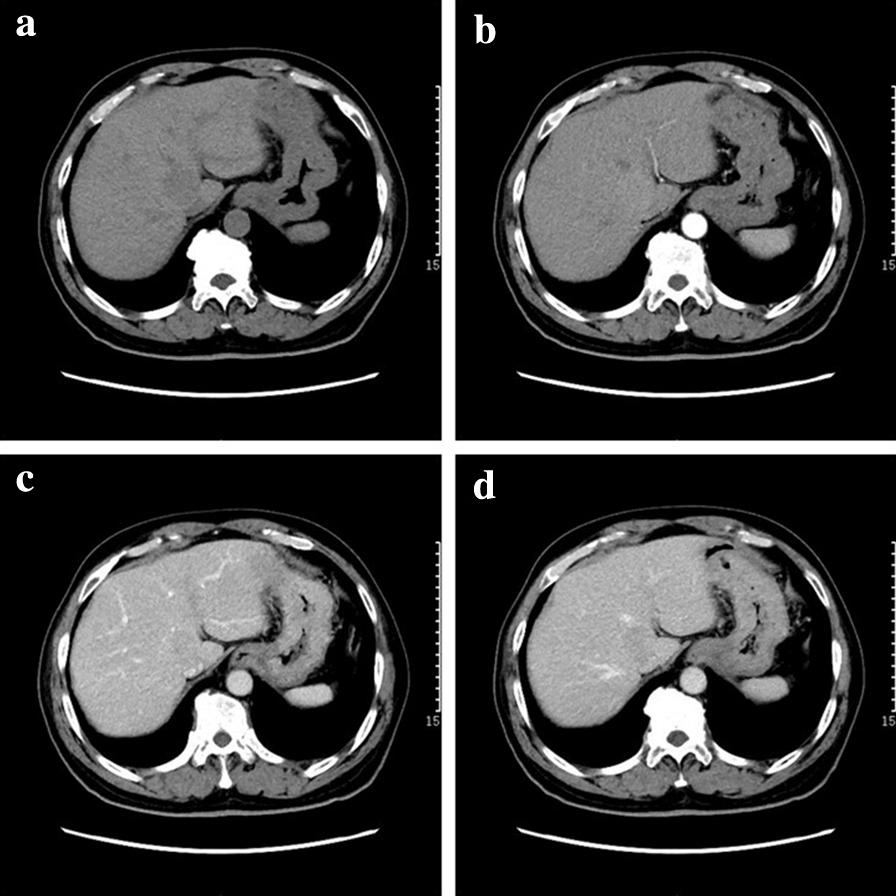

We analyzed two cases of IPT-like FDCS in the liver, nine in the spleen, and two in both the liver and spleen concomitantly. IPT-like FDCS presented as well-defined iso- or hypodense masses on unenhanced computed tomography (CT) images in both the liver and spleen. Hyperintensities on T1-weighted images and hypointensities on T2-weighted images with hypointense rings were characteristic features in splenic cases. "Halo signs" were observed in two out of three liver tumors. Hepatic lesions showed significant enhancement, whereas splenic lesions showed only mild enhancement. Delayed annular enhancement was observed in both liver and spleen cases. On ultrasonographic examination, IPT-like FDCS presented as hypoechoic lesions with enhancement similar to that observed on CT. Hyaline fibrous pseudocapsules, which correlated with the hypointensities on T2-weighted images, were microscopically observed at the tumor edge. IPT-like FDCS was characterized by an abundance of small blood vessels and capillaries. Capillaries were also found in the fibrous capsule of some IPT-like FDCSs, which may explain the delayed annular enhancement.

The manifestations of IPT-like FDCS in the liver and spleen showed differences that warrant them to be approached differently during diagnosis. Characteristic radiological findings of IPT-like FDCS included different enhancement patterns between liver and spleen tumors and rim-like hypointensities on T2-weighted images, as well as annular enhancement on CT and magnetic resonance images. These imaging features correlated with tumor pathology.